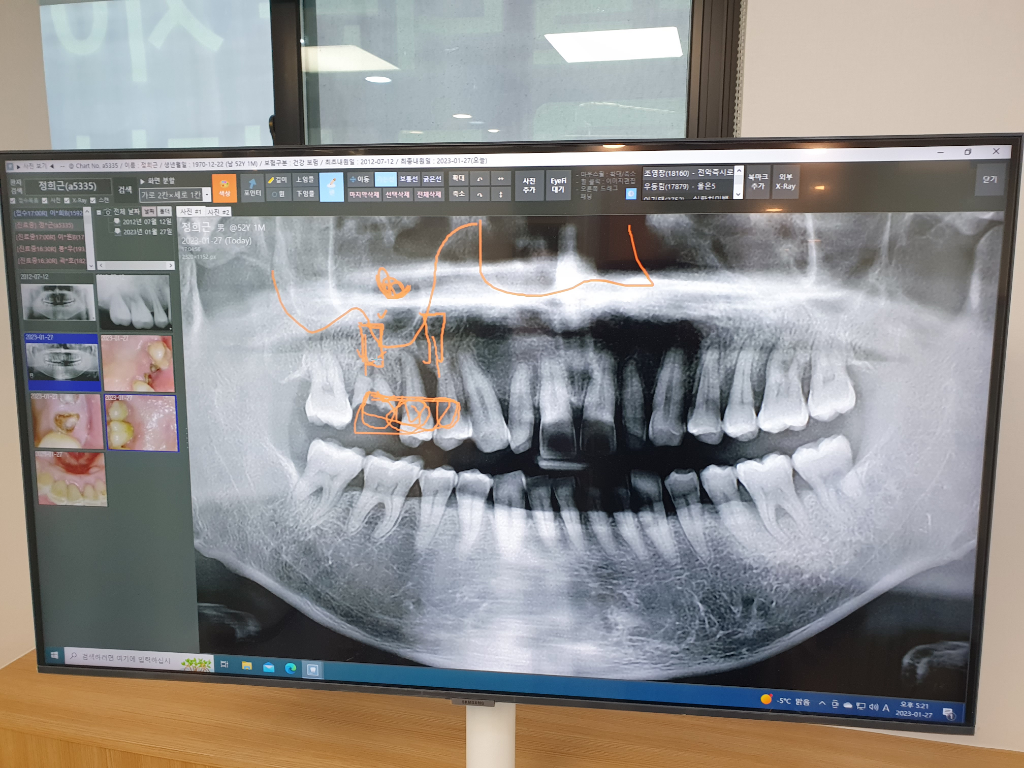

임플란트 2개 보철1개 상악동 뼈이식 수술 문의

사진처럼 윗몸 어금니 3개 발치하고 2개 임플란트 및 1개 보철로 하고 상악동 및 뼈이식 한다고 하는데 하루에 수술 다 한다고 합니다. 혹시 이틀에 걸쳐서 해도 될까요. 보험금 지급이 수술 회당 지급이라 2회로 하면 보험금으로 치료가 어느정도 카바될듯합니다. 의견 감사합니다.

• 1번 째 사진